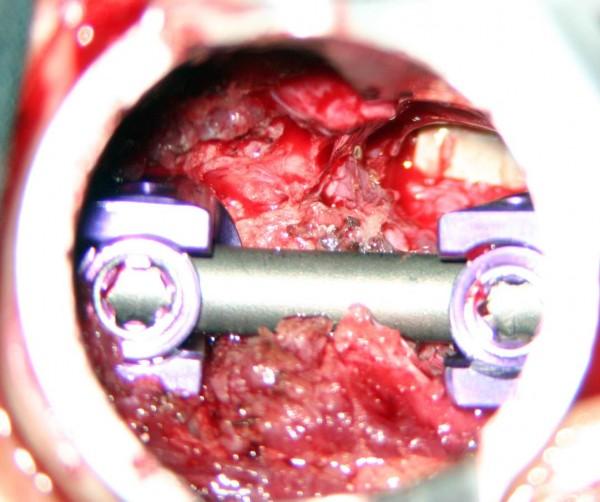

Este tipo de cirugías de la columna vertebral usualmente requiere del uso de varillas y tornillos metálicos para evitar el movimiento y permitir que se lleve a cabo la fusión del injerto de hueso. También es importante mencionar que una cirugía de fusión espinal pueden ocasionar una disminución mínima en la flexibilidad de la columna vertebral, pero a pesar de ello, muchas personas que se han sometido a este procedimiento indican una mayor flexibilidad como consecuencia de que ya no experimentan dolor en la espalda ni tampoco espasmos.

Los injertos de hueso son fundamentales en la fusión de la columna vertebral y suelen utilizarse de dos formas principalmente: Para estimular la médula y Para prestar apoyo a la estructura mediante el rellenado de los huecos entre los huesos. Los injertos de hueso también son utilizados para la estructura, por lo que es común que grandes partes de hueso sean utilizadas para rellenar los huecos entre los dos huesos. En caso de que el cirujano retire una vertebra o un disco, puede utilizar un injerto de hueso para rellenar dicho espacio que ha quedado vació por así decirlo.

Ya que el hueso es rígido, los huesos separados se sostienen, mientras que el cuerpo se fusiona con el injerto de hueso en cada extremo. Con el paso del tiempo, todo el injerto del hueso es remodelado y de hecho reemplaza el hueso y el disco que fue inicialmente removido.